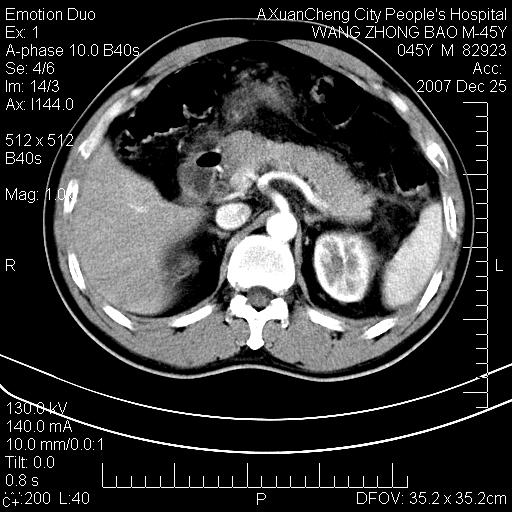

以下是引用qiuleiyu在2007-12-25 18:14:00的发言:[br]胰腺增大,周边渗出改变,肾前筋膜明显增厚,示少量积液.胆囊壁毛糙,周边少许渗出,胆总管壁厚,异常强化,然扩张不明显.结合病程急短;考虑;胆管炎,胆囊炎,胆源性胰腺炎可能大,请结合实验室检查及随访.

以下是引用lisihao在2007-12-25 14:23:00的发言:[br]急性水肿型胰腺炎[br]依据:1、胰腺弥漫性肿大,边缘稍毛糙;[br] 2、双侧肾周筋膜增厚,尤以左侧为甚(重要征象)[br] 3、双侧后胸膜增厚(刺激性炎症);[br] 4、结合病史,查血尿淀粉酶应该可以确诊。